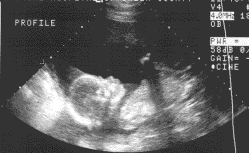

pre natale echo

Opvolging van de groei van de foetus tijdens de zwangerschap